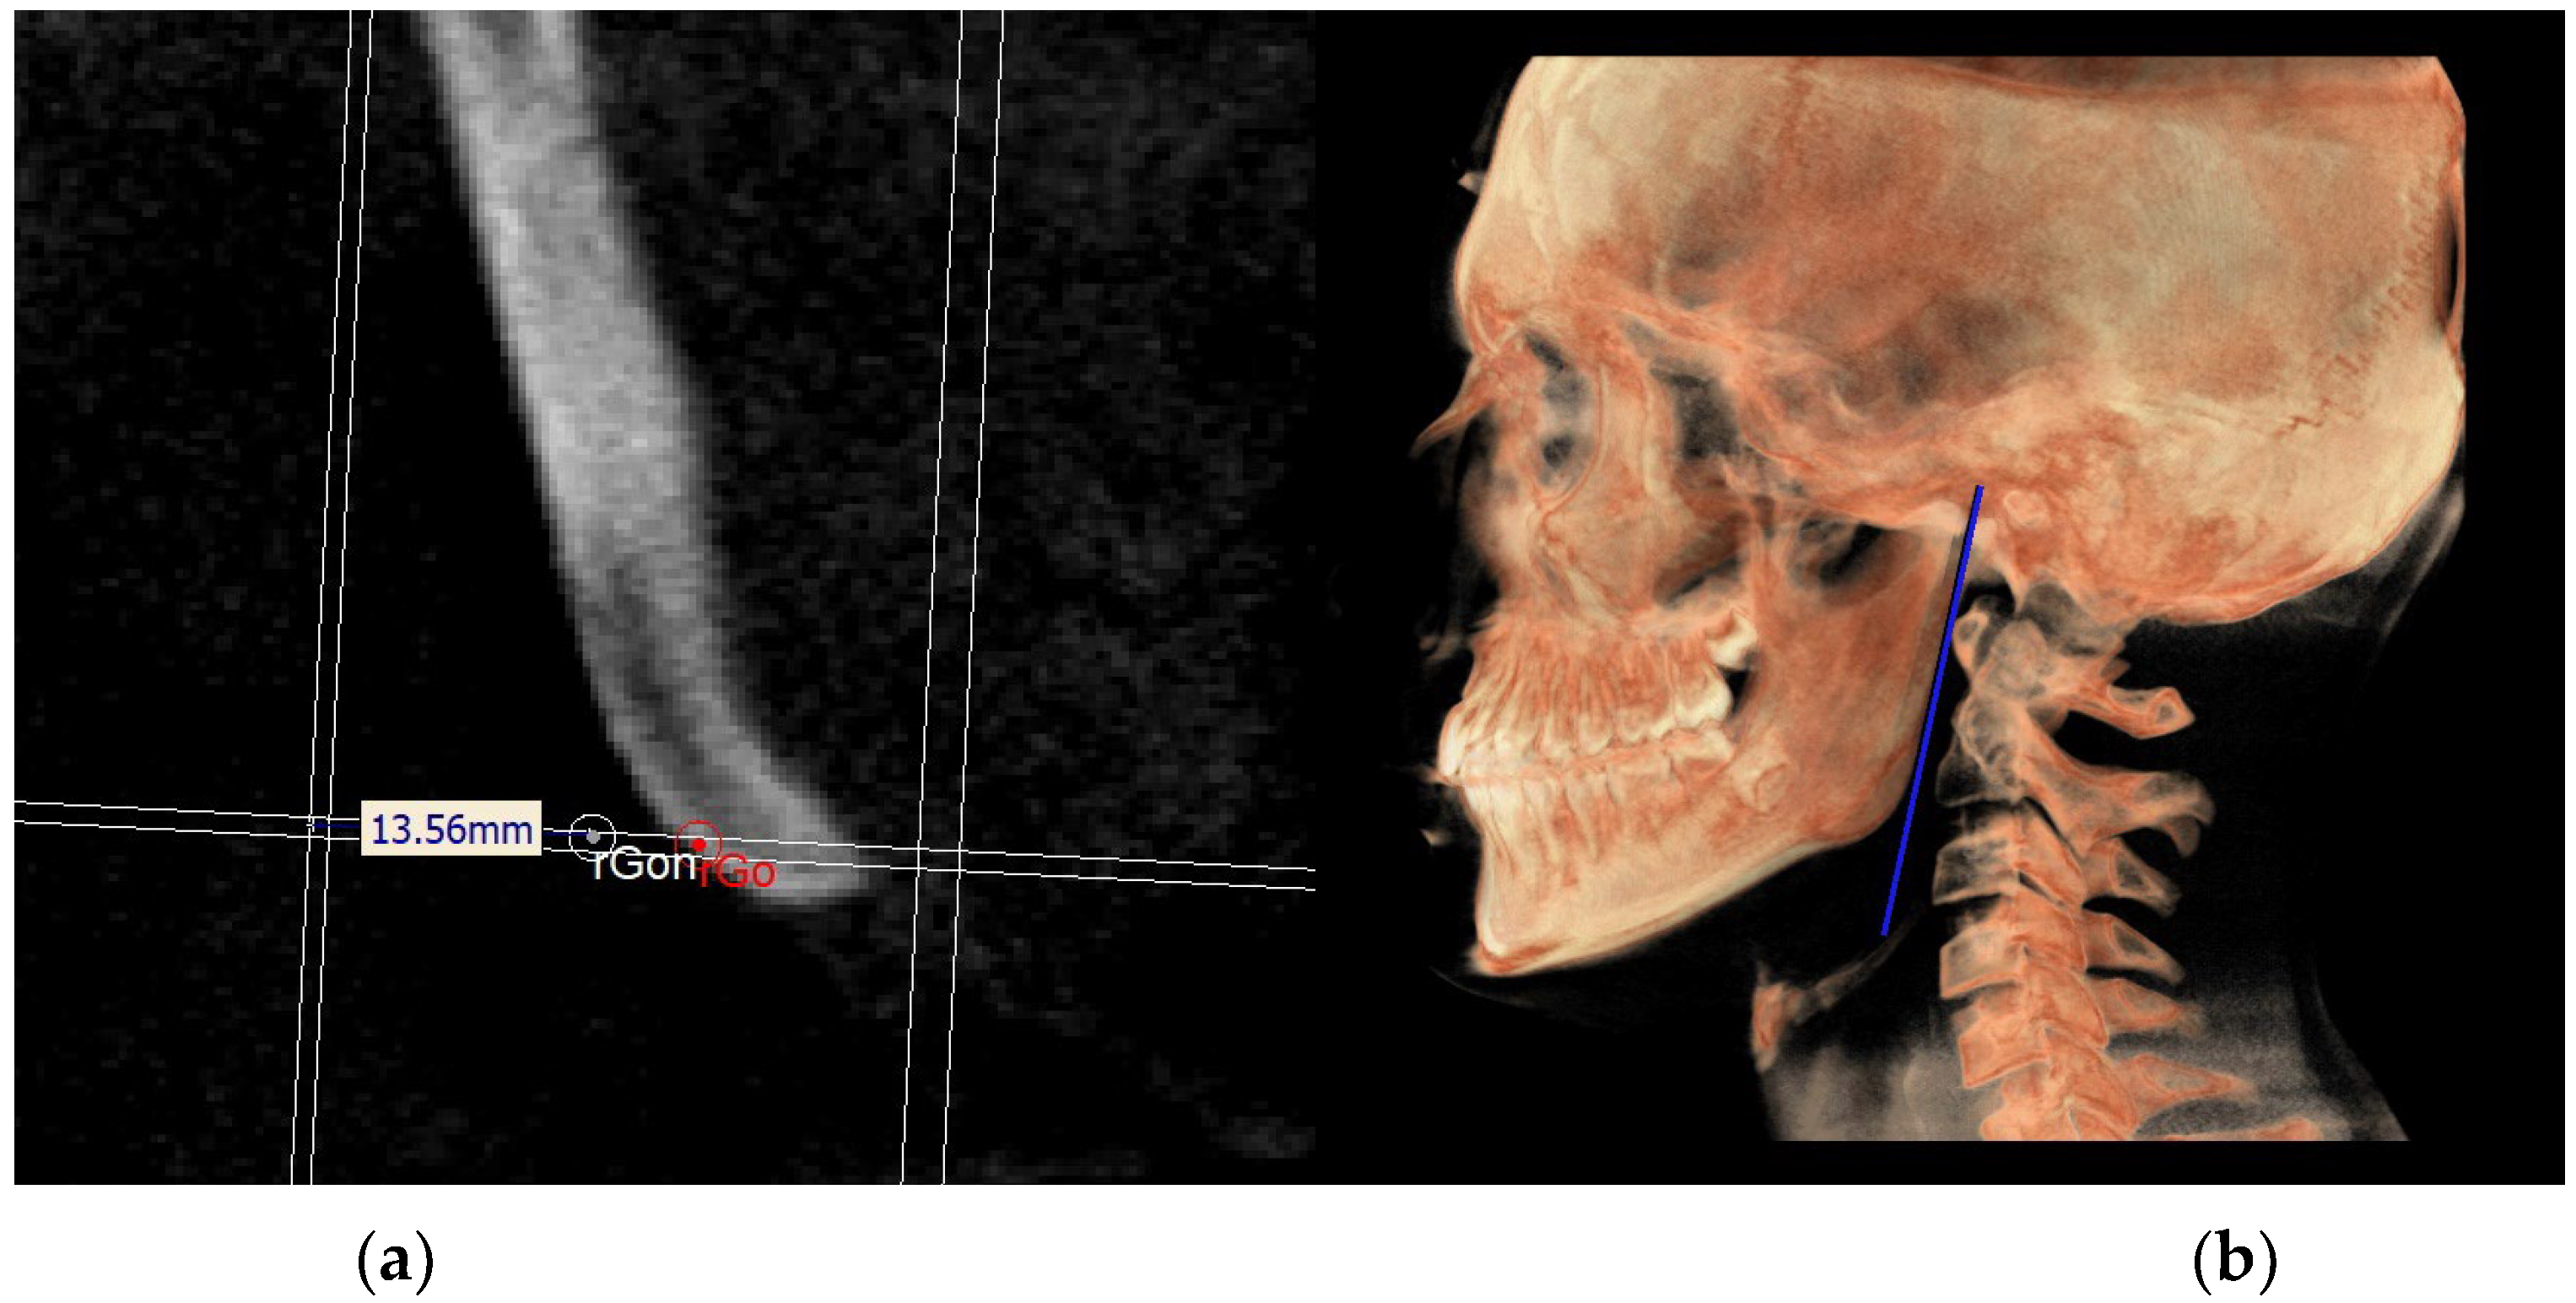

- The mandibular ramus plane (MR) (Figure 5) was identified by the following points: the middle points between the right and left condylion (mCo) and the right Gonion (rGo) and left Gonion (lGo). To adequately locate the mCo, it is advisable to draw a line on the frontal view from the right condylion to the left one to have a reference along which measure the mid-distance;

| Gon | Gonion neutral: the point located at the same level of the Go and halfway between the PMn line and its parallel passing through Ar |

| MRn | MR neutral, Ar—Gon |

| Right gonion (rGo) | Point at inferior border of mandibular angle at mid-distance between posterior-inferior-most point of ramus and inferior-posterior-most point of mandibular body, right side | Middle-posterior-most point of mandibular angle, right side | Middle-inferior-most point of mandibular angle, right side |

| Left gonion (lGo) | Point at inferior border of mandibular angle at mid-distance between posterior-inferior-most point of ramus and inferior-posterior-most point of mandibular body, left side | Middle-posterior-most point of mandibular angle, left side | Middle-inferior-most point of mandibular angle, left side |

| Neutral right gonion (rGon) | Point located at the same level of the Go and halfway between the PMn line and the CPCo plane. Right side | / | / |

| Neutral left gonion (lGon) | Point located at the same level of the Go and halfway between the PMn line and the CPCo plane. Left side | / | / |

| MR neutral (MRn) | Plane passing through the mCo, rGon and lGon |